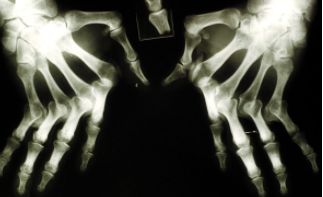

4关节影像学检査

早期类风湿关节炎影像学改变常不明显且不典型,X线表现与病情进展也不完全平行。

河南类风湿医院介绍典型的类风湿关节炎诊断并不困难,可参考1987年美国风湿病学会的分类标准,但该标准并非具有100%的特异性和敏感性。尽管类风湿因子已被多数临床医师作为诊断类风湿关节炎的重要依据,但IgG抗体并无特异性。所以,不能简单地把有关节痛和类风湿因子“阳性”的患者与类风湿关节炎画等号。符合典型类风湿关节炎的各种表现的患者并不多见,特别是早期患者。对不典型患者,应了解详细的病史、进行体格检査和必要的实验室及其他检査。类风湿因子阳性虽不能作为确诊的依据,但可作为有价值的线索,拍摄手足X线片对早期确诊有帮助,滑膜液分析和组织病理检査均是必要的诊断手段。随着医学的进步,专家们发现如果严格按照上述标准,大约有30%的患者会漏诊,从而失去最佳治疗时机。

因此,人们又努力寻求到了早期类风湿关节炎的诊断指标,CT和MRI的广泛使用可使确诊的时间大大提前。所以,得了类风湿做哪些检查项目,现在临床上诊断类风湿不是机械地照搬标准,而是在参考上述标准的同时结合具体情况,进行一些必要的检査,同时排除系统性红斑狼疮、干燥综合征、强直性脊柱炎、骨关节炎、痛风、风湿热、风湿性多肌痛等其他风湿性疾病,以此方能达到更髙的诊断率。